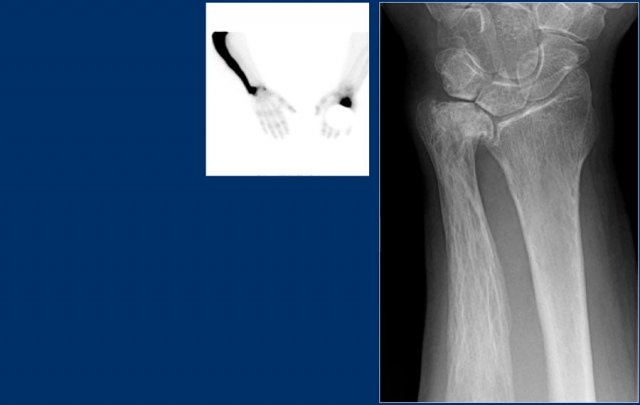

Study the images and then continue reading.

The findings are:

• Pathognomonic triad of bone expansion, cortical thickening and trabecular bone thickening.

• This is the mixed lytic and sclerotic phase of Paget.

• Positive bone scan.

Here we see broadening of the ulna shaft is seen with a mixed lytic-sclerotic appearance and coarse trabeculation.

Differential diagnosis based on the radiograph:

1. Paget's disease

2. Fibrous dysplasia

The intense uptake of the tracer on the bone scintigraphy makes the diagnosis of Paget's disease the most likely.